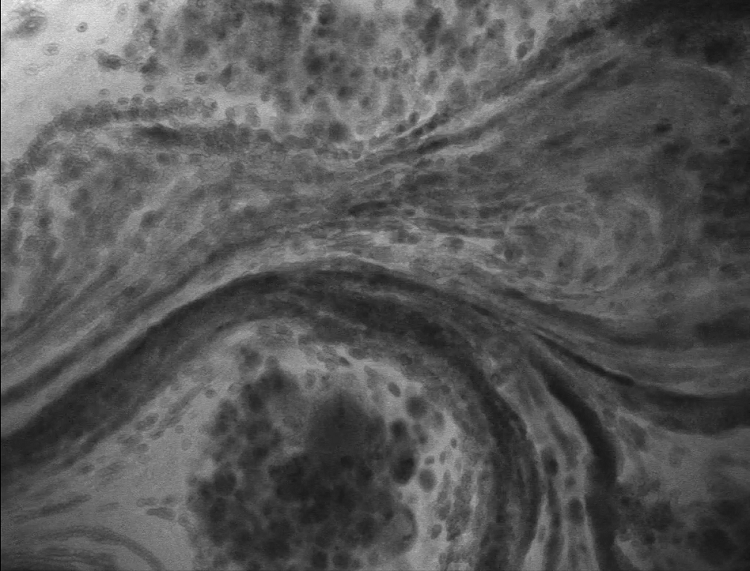

8、脑胶质母细胞瘤OptiScan成像

注:活大鼠脑中被渗漏血管包围的肿瘤病灶。该肿瘤为恶性胶质瘤,浸润性强,可引起出血。这里使用的造影剂是静脉注射荧光素。在本实验中,注射了IV荧光素。它分布在整个动物周围,可以看到血液通过血管流动。为此,头骨需要被打开或变薄。大型动物的硬脑膜也需要手术打开。Scale bar=100μm。